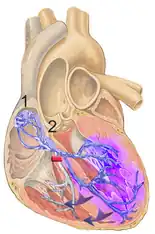

Causes include heart damage, such as a heart attack or myocarditis, increased right ventricular pressure, such as with pulmonary embolism or cor pulmonale, and rarely high blood potassium.[1] Though some cases occurs without any specific cause.[2] The underlying mechanism involves damage to the right bundle branch.[1]